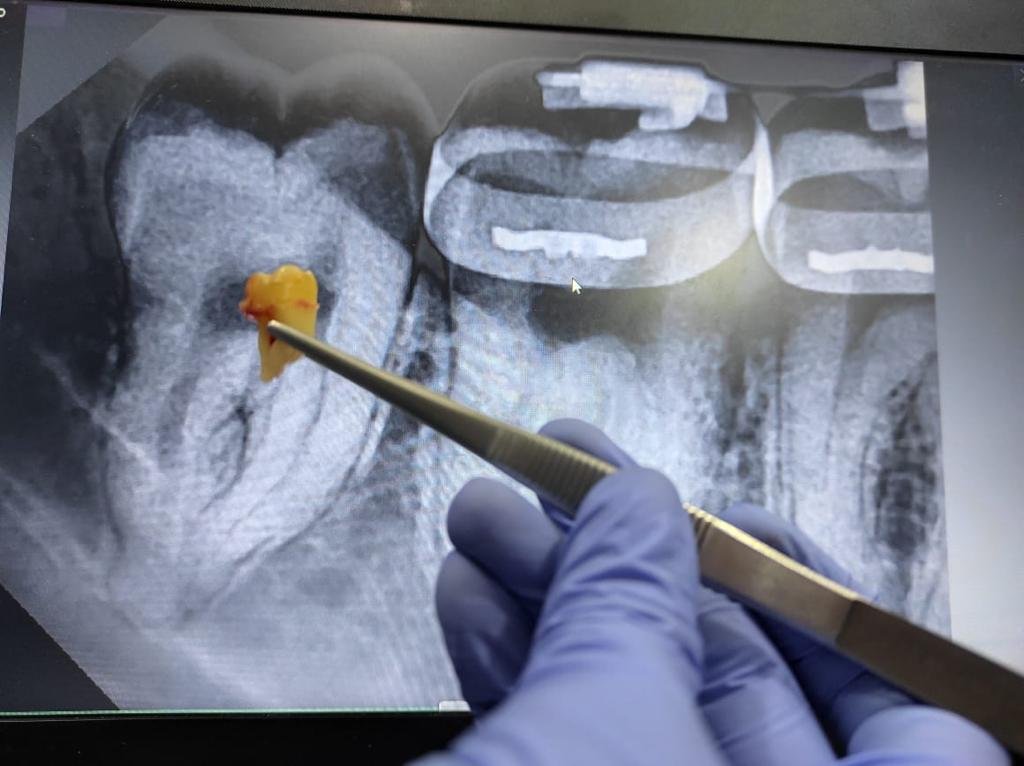

Prosedur odontektomi gigi bungsu di jakarta

Bagaimana Prosedur Odontektomi Dilakukan?

Dokter gigi bedah mulut melaksanakan odontektomi dengan beberapa langkah berikut:

1. Pemeriksaan awal

Dokter melakukan rontgen panoramic untuk melihat posisi gigi bungsu dan menilai kondisi pasien.

4. Pengangkatan gigi

Bila gigi sulit dicabut, dokter membaginya menjadi beberapa bagian lalu mengangkat potongan satu per satu.